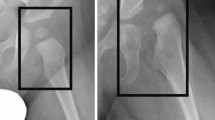

We tried to increase the understanding of the model by using saliency maps. Figure 4 shows examples of saliency maps for Normal/Borderline and Crowe 1–4 classifications. The saliency maps showed that the edge of the calcar region of the femur and its relation to the pelvic ring played an important role in the classification. This seems like a method resembling dysplasia classification by relying on Shenton’s line, which is a method that has high accuracy for determining femoral subluxation [32].

Furthermore, the model seemed to use the inferior cortex of the femoral neck arch and its relation to the inner and outer cortices of the pelvic ring (Fig. 5). For the more dysplastic hips that also had more femoral head deformity, the model seemed to recognize a narrower arch between the neck and the deformed head (Fig. 5, Crowe class 3). Although these interpretations are highly subjective and cannot be interpreted as a “logic” being used by the model, it is encouraging to see that the model learned to focus on relevant anatomical areas without any explicit training or “rules” to follow.